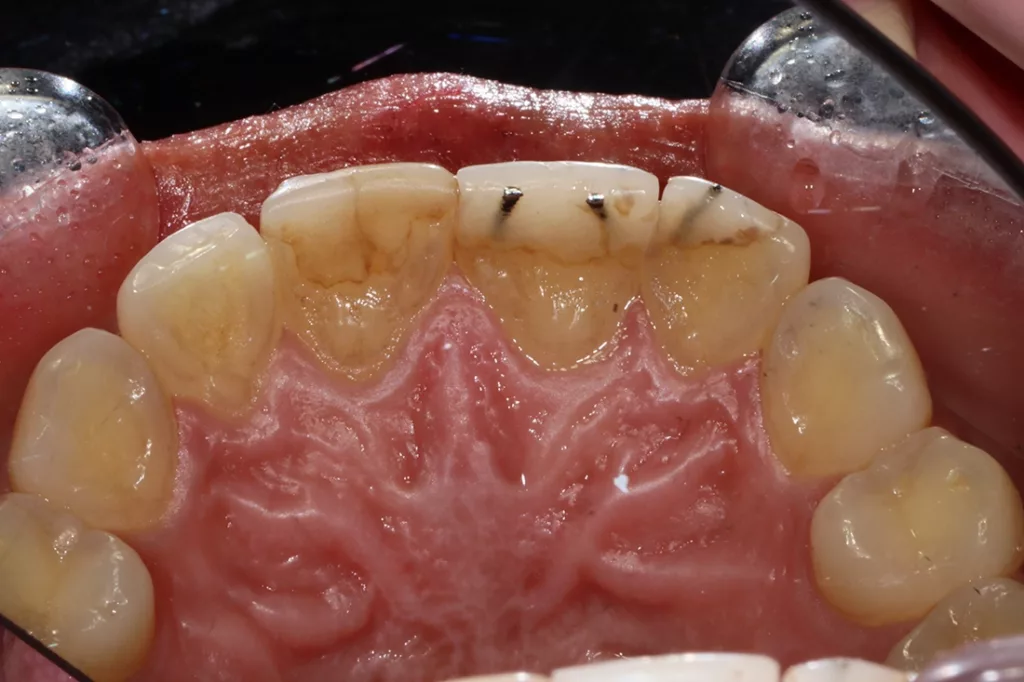

Darüber hinaus schimmerte die graue Farbe der Stifte durch den Kunststoff hindurch. Als Folge harmonierten die Inzisallinien der 4 Schneidezähne nicht mehr mit der unteren Lippenlinie. Vermutlich war eine unzureichende Frontzahnführung Ursache dafür, dass der Kunststoff wiederholt absplitterte und ein Inserieren von Stiften notwendig war, was damit ein dauerhaftes Problem darstellte. Die Patientin fühlte sich mit ihrem Lächeln sehr unwohl und suchte nach einer Behandlungsmöglichkeit, mit der ein ästhetisch ansprechenderes und natürlicheres Ergebnis erzielt werden konnte (Abb. 51 und 52).

Die ursprüngliche Planung sah vor, den alten Kunststoff und den Metallstift im Schneidezahnbereich behutsam zu entfernen, ohne dabei die gesunden Zähne zu beeinträchtigen. Beim Entfernen ging jedoch vor allem an Zahn 12 und 11 unerwartet viel Zahnsubstanz verloren. Dementsprechend musste die Behandlungsmethode angepasst werden. Ein bestmögliches Ergebnis versprach nach einer Zahnaufhellung die Versorgung der oberen Schneidezähne mit 4 Zirkoniumdioxidkronen.

Um die Zähne 21 und 22 so vital wie möglich zu erhalten, wurden sie rundum lediglich um ca. 1,5 mm reduziert. Bei den Zähnen 11 und 12 war dies vor allem inzisal nicht möglich, da sie nach der Entfernung des Metallstiftes und des Kunststoffes stark reduziert waren, jedoch nicht so stark, dass eine Wurzelbehandlung notwendig gewesen wäre. Die Zähne wurden anschließend mit neuen Kunststoffaufbauten versorgt und für monolithische Zirkoniumdioxidkronen präpariert. Während der provisorischen Versorgung wurden die Zähne regelmäßig kontrolliert, um den Erfolg der Restauration und das Ausbleiben von Komplikationen sicherzustellen (Abb. 53 bis 56).